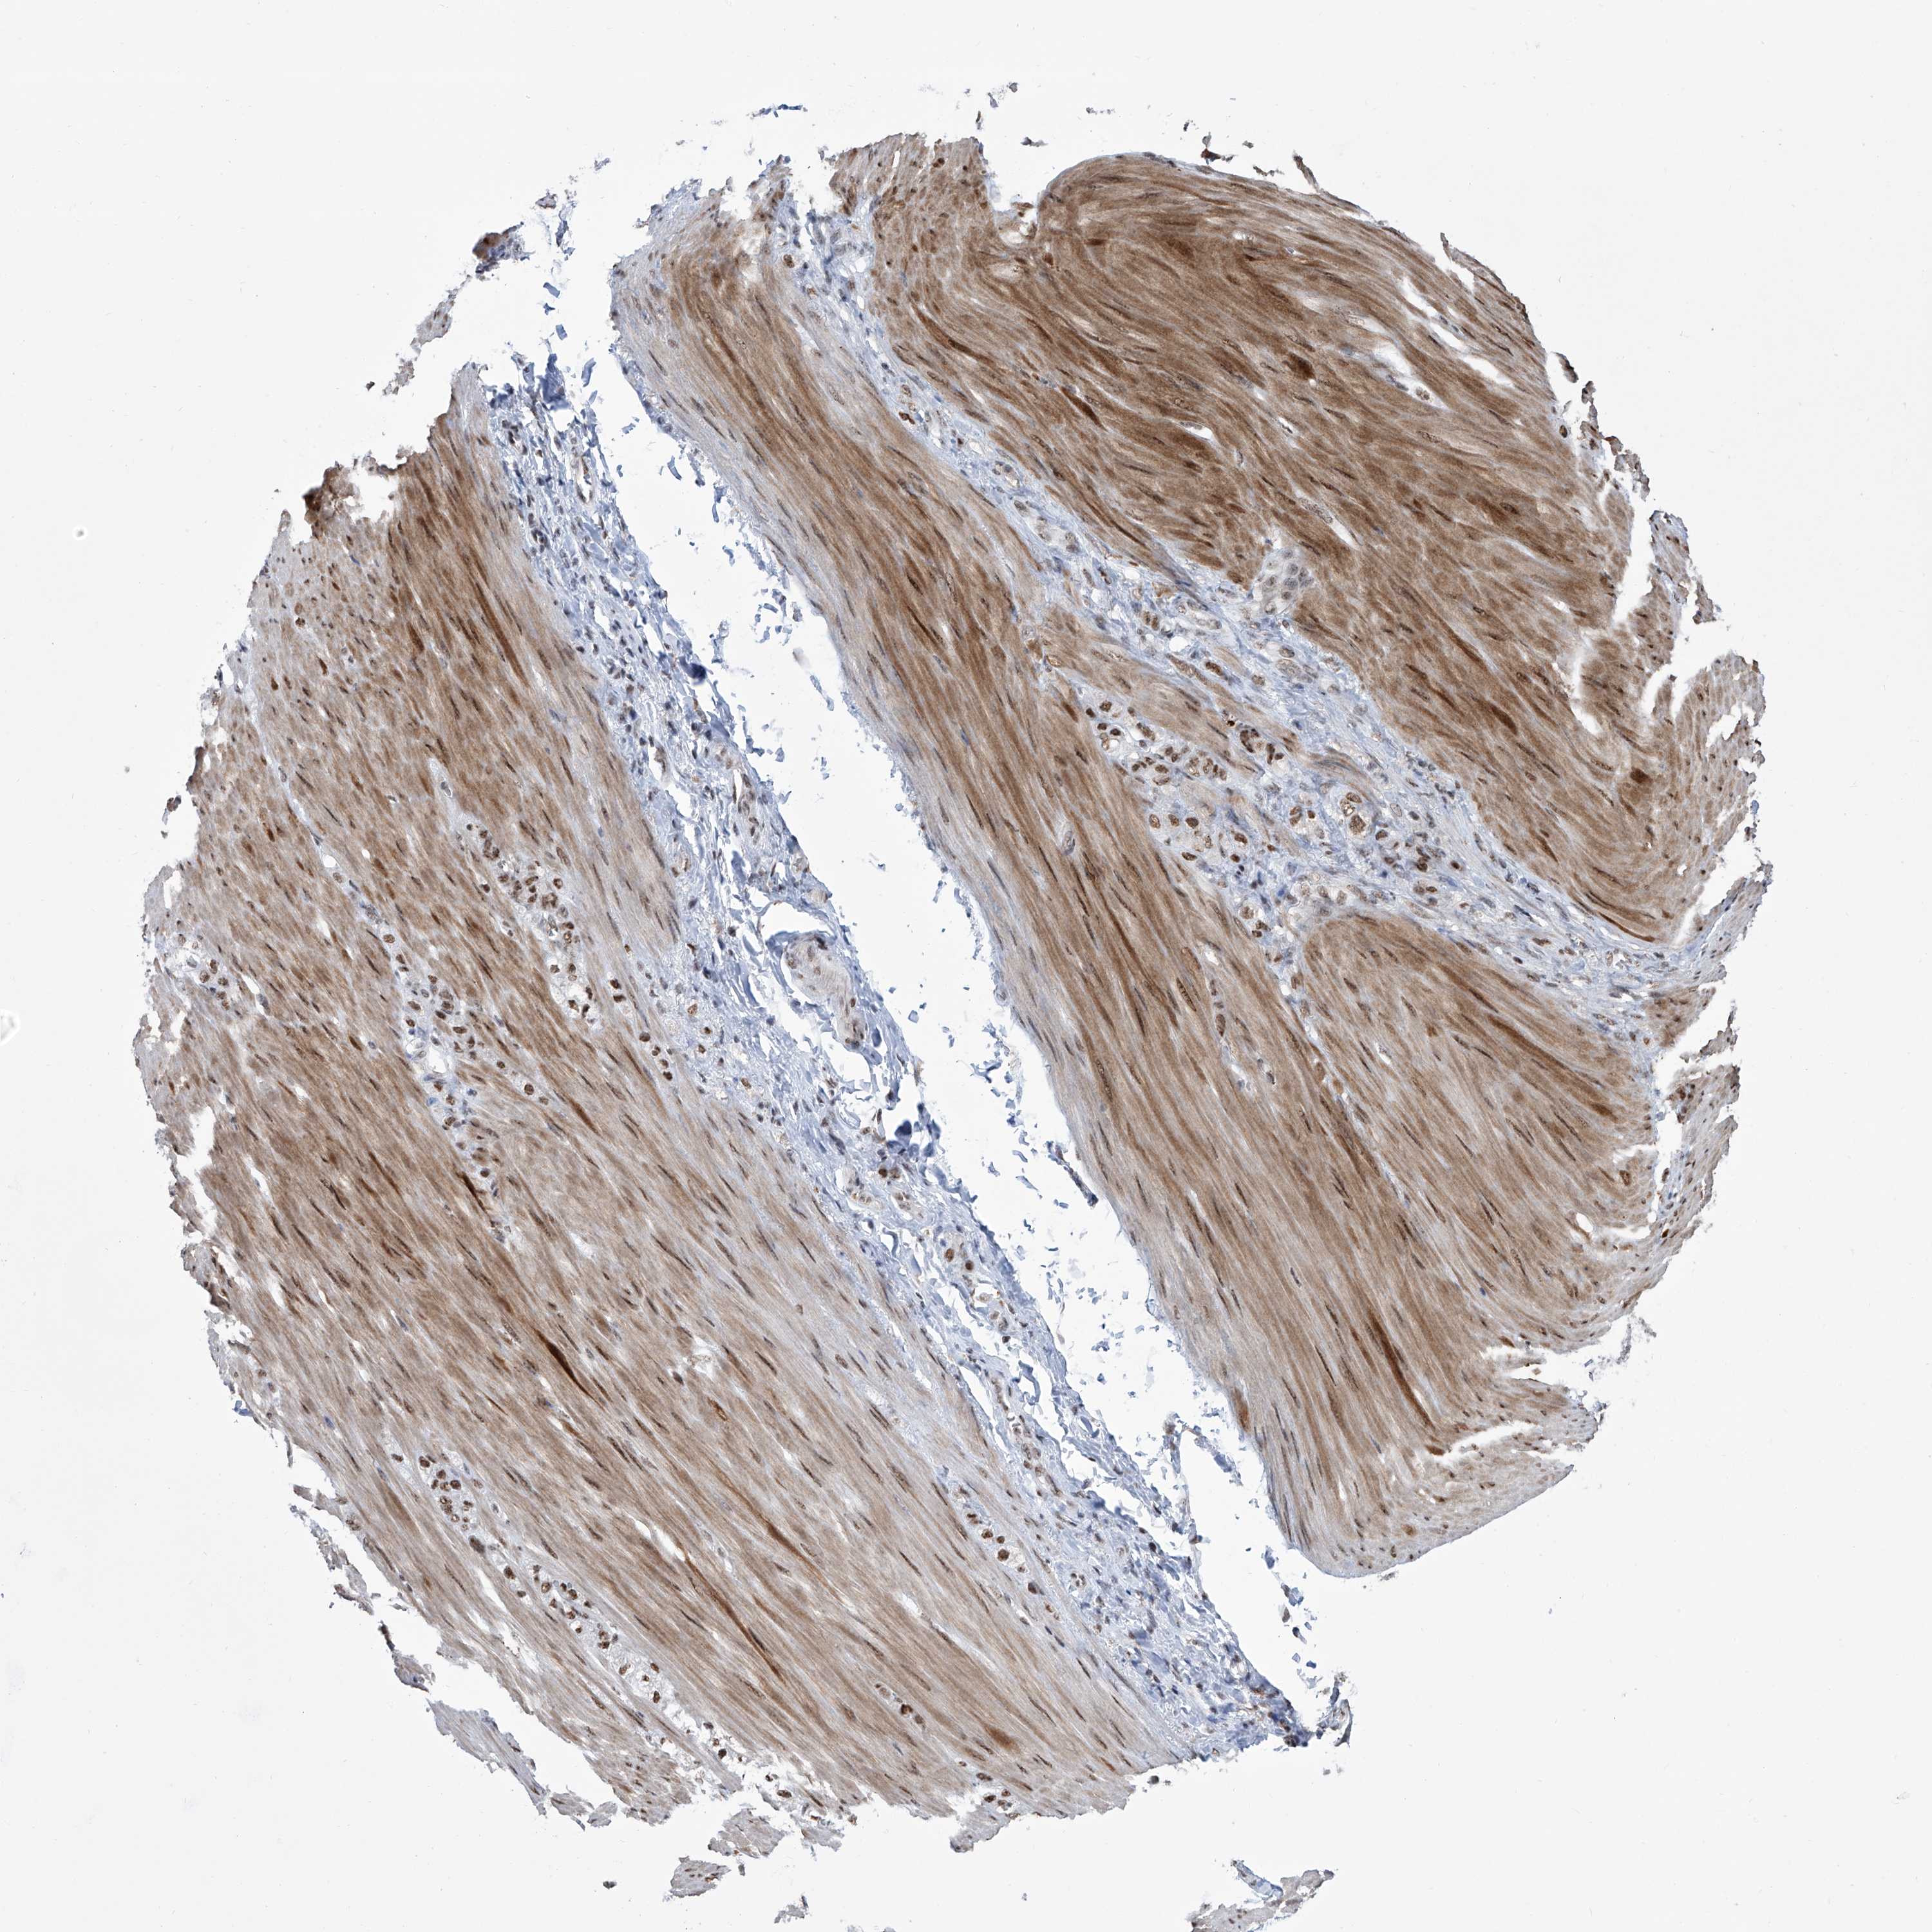

STOMACH CANCER - Protein expressioni

A mouse-over function shows sample information and annotation data. Click on an image to view it in a full screen mode. Samples can be filtered based on level of antibody staining by selecting one or several of the following categories: high, medium, low and not detected. The assay and annotation is described here.

Antibody stainingi

Antibody staining in the annotated cell types in the current human tissue is reported as not detected, low, medium, or high, based on conventional immunohistochemistry profiling in selected tissues. This score is based on the combination of the staining intensity and fraction of stained cells.

Each image is clickable and will lead to virtual microscopy that enables deeper exploration of all samples and also displays staining intensity scores, fraction scores and subcellular localization as well as patient and tissue information for each sample.

Antibody HPA029140

Antibody CAB033362

Staining

High

Medium

Low

Not detected

Intensity

Strong

Moderate

Weak

Negative

Quantity

>75%

75%-25%

<25%

None

Location

Nuclear

Cytoplasmic/membranous

Cytoplasmic/membranous,nuclear

Adenocarcinoma, NOS

Adenocarcinoma, High grade